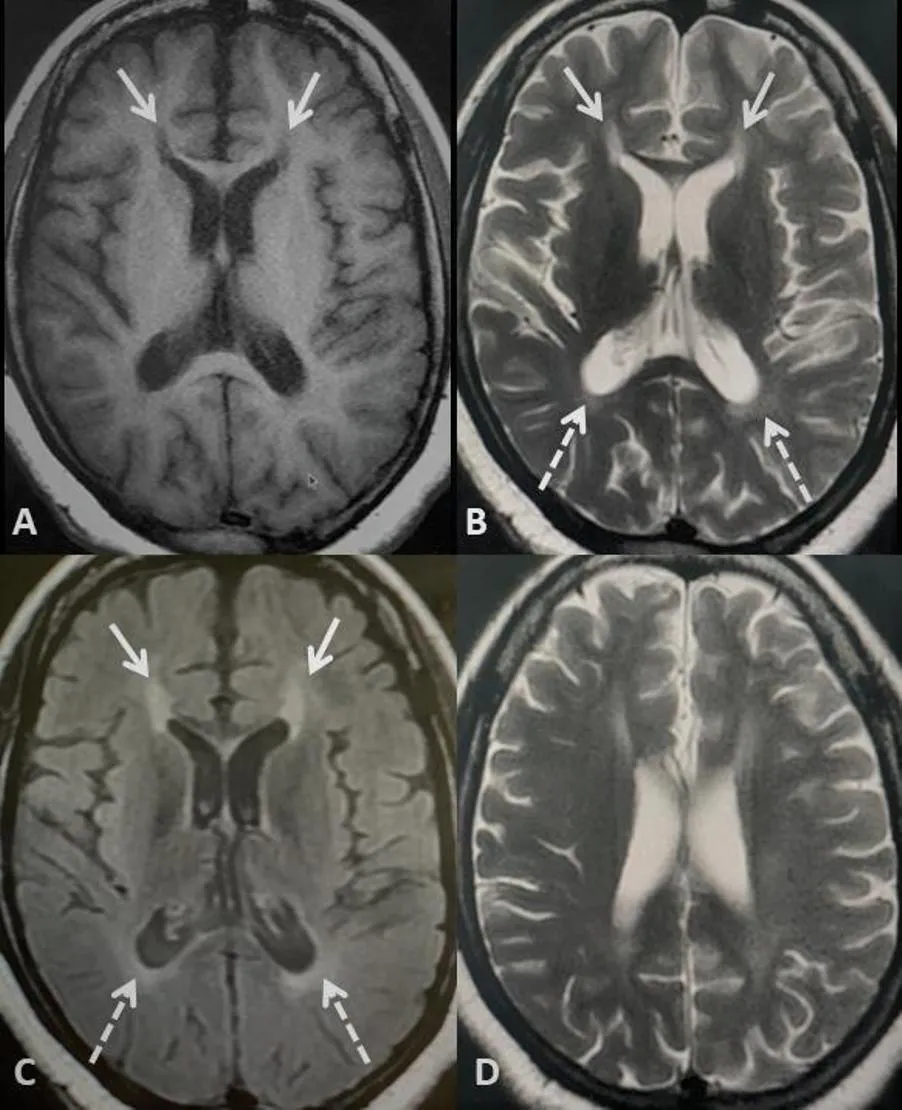

图1 轴位T1加权像(A)、轴位T2加权像(B)及轴位T2-FLAIR加权像(C)显示胼胝体膝部小钳区(箭头所示)存在特征性信号异常。该信号异常在T1加权像上呈低信号,在T2/FLAIR加权像(液体衰减反转恢复序列)上呈高信号,呈现典型的‘火焰’样形态,与猞猁耳特征极为相似。此外,还可见脑室周围白质高信号,尤其在枕角区域(虚线箭头所示)。另,头侧轴位T2加权像(D)显示轻度全脑萎缩,表现为脑沟间隙及脑室体积相对于年龄而言增大。